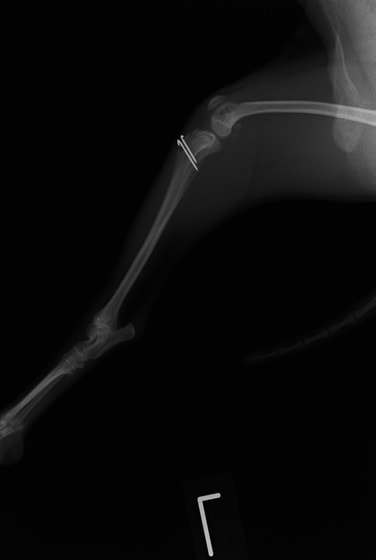

■ 症例20 ポメラニアン 8ヶ月 1.8kg

左右膝蓋骨脱臼 グレードⅢ

2ヶ月前から間欠的跛行が認められ、両膝の膝蓋骨脱臼整復術を行った。

手技は縫工筋及び内側広筋の解放、脛骨粗面の外側転位、滑車ブロック形造溝術、内外側関節包の縫縮を選択し実施した。

右側の膝蓋骨脱臼は上記手技で整復されたものの、左側はそれのみでは膝蓋骨が浮く様子が認められた。その為、PDS縫合糸にて膝蓋靱帯を1糸のみ縫合し、靱帯の縫縮を行った。

膝蓋骨脱臼は膝関節における膝蓋骨の内外側の脱臼と定義されるが、時として単純な内外の脱臼ではなく、膝蓋骨が大きく前方に浮き上がるように脱臼する場合がある。特にトイプードルやポメラニアンといった犬種に多く認められる。

内側脱臼に加えて前方への浮き上がりを矯正する為に、従来より脛骨粗面転移により膝蓋靭帯を外方と下方に引っ張り、固定する方法を選択する。膝蓋骨の前方への浮き上がりが軽度の場合は、従来法ではなく関節包の縫縮で対応していた。しかし、一部の症例で膝蓋骨の動きが悪くなり伸展機構が円滑に機能せずロボット様歩行になるケースがあった。

その為、膝蓋靭帯自体を縫縮する方法を採用した。この方法により、膝関節の伸展機構を妨げず膝蓋骨の軽度の浮きを矯正することが可能となった。

本症例の経過は良好である